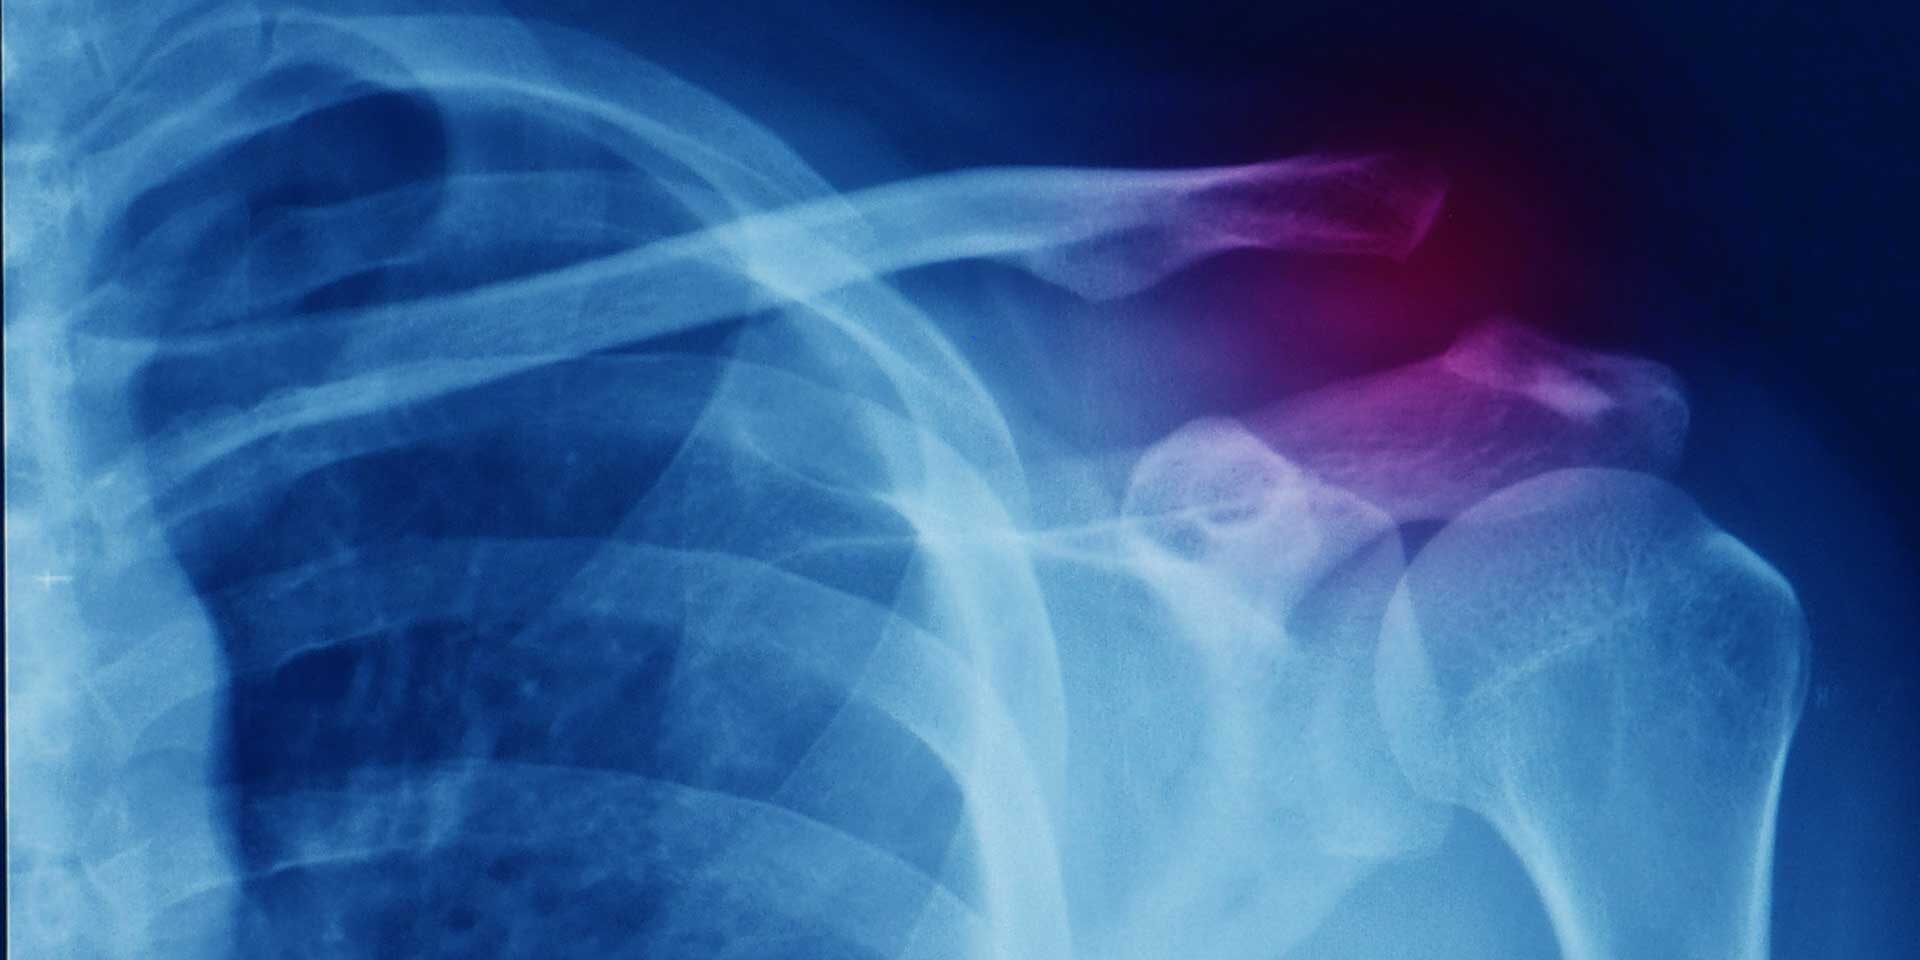

Les disjonctions acromio-claviculaires sont des pathologies fréquentes suite à des traumatismes chez les jeunes sportifs. Quel est le meilleur traitement après une entorse ou une luxation acromion-claviculaires en fonction du grade de gravité ? Frédéric Srour Kinésithérapeute et Geoffroy Nourissat Chirurgien orthopédiste, tous deux spécialisés dans la prise en charge des pathologies de l’épaule, répondent en 3 minutes à ces questions